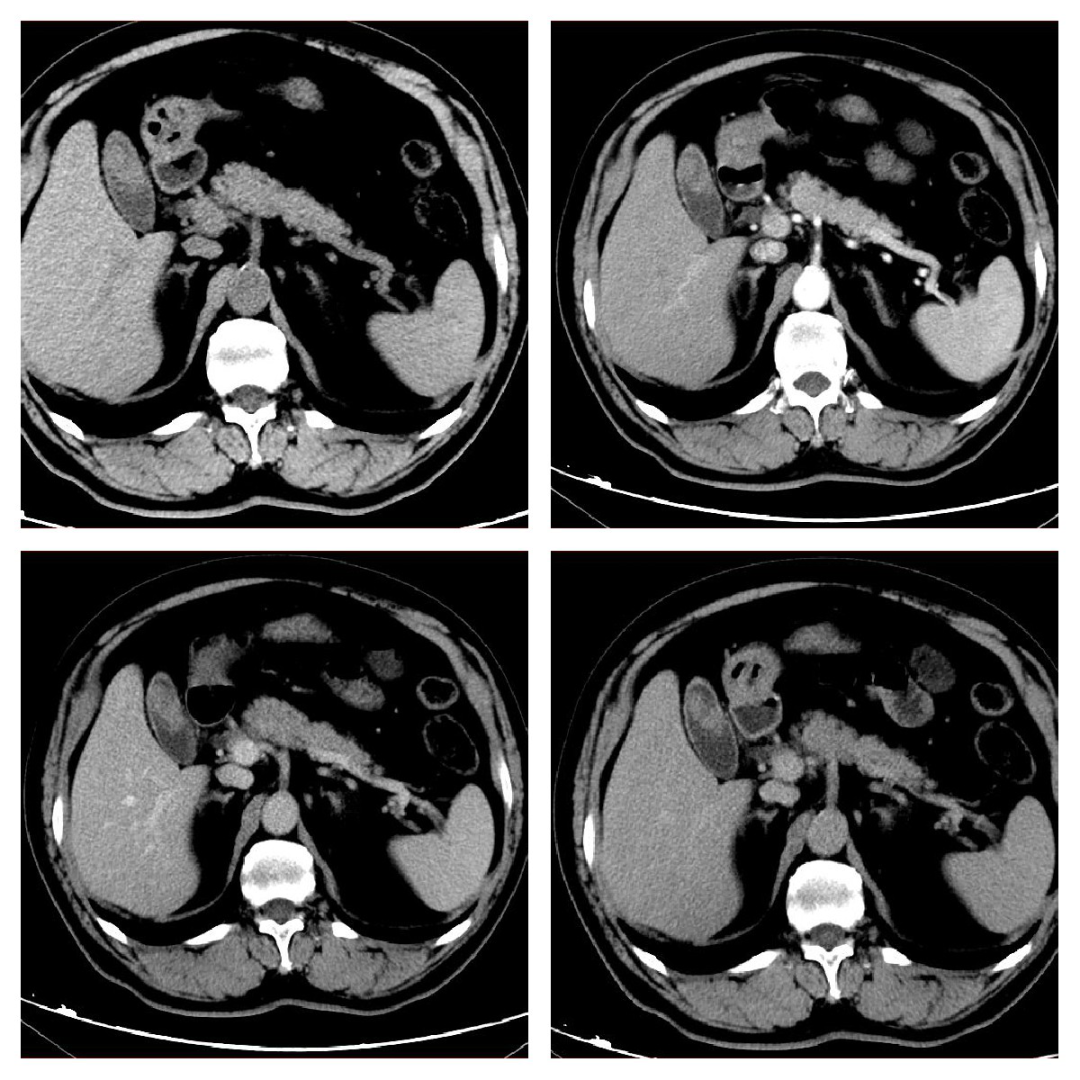

胰腺癌:胰腺是富血供器官、胰腺癌是乏血供肿瘤,因此表现为低信号肿物。

胰腺囊腺瘤:常常表现为壁可见强化的囊性肿物,容易与囊肿混淆。